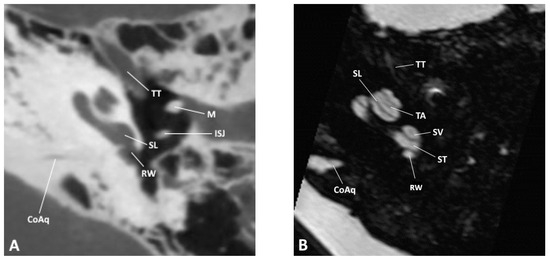

Figure 3. Sagittal slice through the inner and middle ear at the level of the vestibule as observed by (A) CBCT and (B) MRI; CC, common crus; DR, ductus reuniens; FN, facial nerve; GG, geniculate ganglion; PACr, posterior ampullary crest; PBA, posterior bony ampulla; PMA, posterior membranous ampulla; RW, round window; SaM, saccular macula; SSCC, superior semicircular canal; SSCD, superior semicircular duct; SVN, superior vestibular nerve.